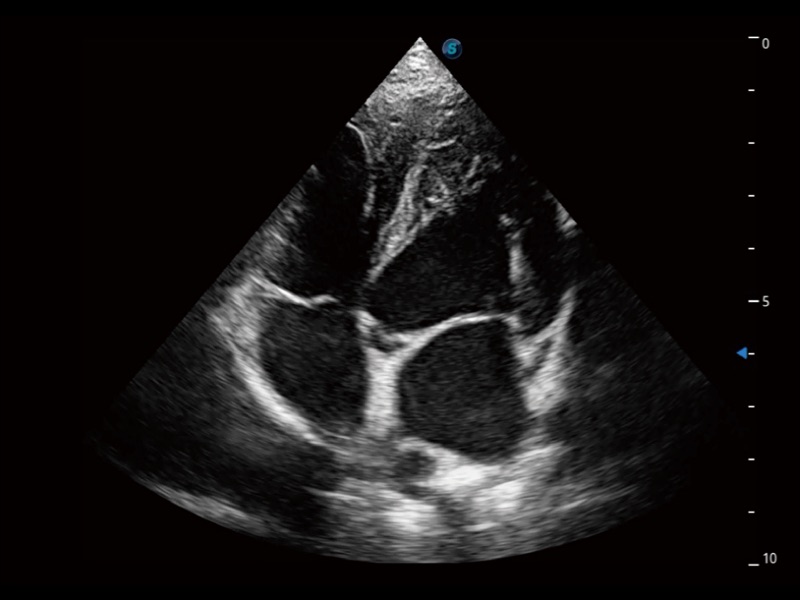

(犬)肾脏显微血流

(猫)胆囊

(猫)肺动脉血流频谱

(犬)左室长轴血流

(犬)髂动脉血流

(犬)四腔心

(犬)胎儿主动脉弓立体血流

(犬)肝脏

(犬)四腔心MQA